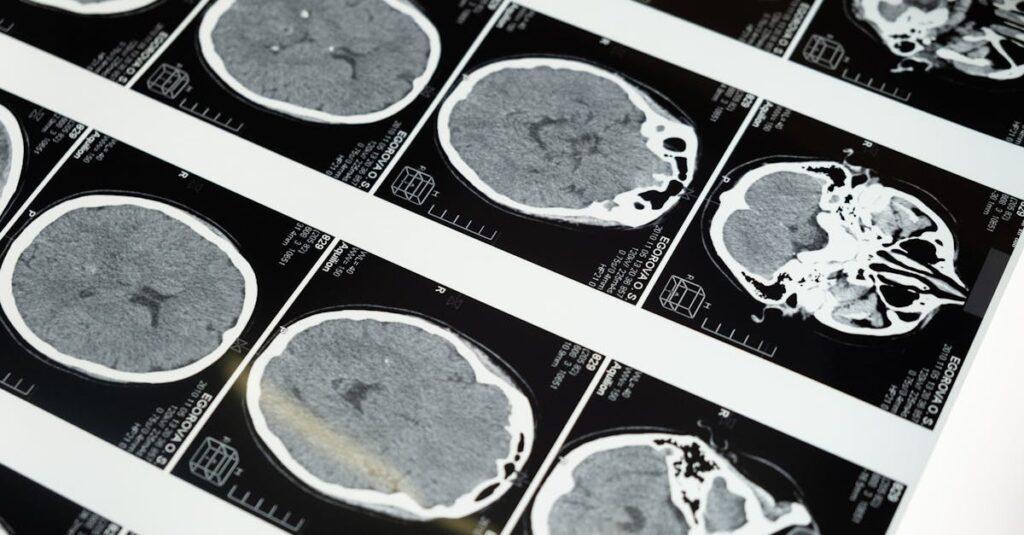

Il est utile de commencer par une évidence : le cortex cérébral est la couche externe du cerveau, une pellicule de substance grise qui recouvre les deux hémisphères. Malgré son épaisseur modeste — seulement quelques millimètres — il représente une part considérable du fonctionnement mental. Les chercheurs estiment qu’il contient entre 14 et 16 milliards de neurones, un nombre qui aide à comprendre sa puissance de traitement.

La surface n’est pas lisse : elle est richement plissée en crêtes (les gyri) et en sillons (les sulci). Cette configuration augmente la surface disponible et permet d’accueillir davantage de neurones sans augmenter le volume. Ces détails morphologiques ne sont pas décoratifs : ils se lient à la façon dont l’information est distribuée.

Si l’on place cela dans une perspective contemporaine, les outils d’imagerie de 2025 permettent d’observer des différences fines de structure et de connectivité. Des études récentes associent la taille relative, l’épaisseur corticale ou la densité de matière grise à certaines performances cognitives, sans pour autant réduire l’intelligence à un seul chiffre. Pour aller plus loin sur ces liens entre structure et cognition, on peut consulter un dossier dédié sur la taille du cerveau et les performances cognitives.